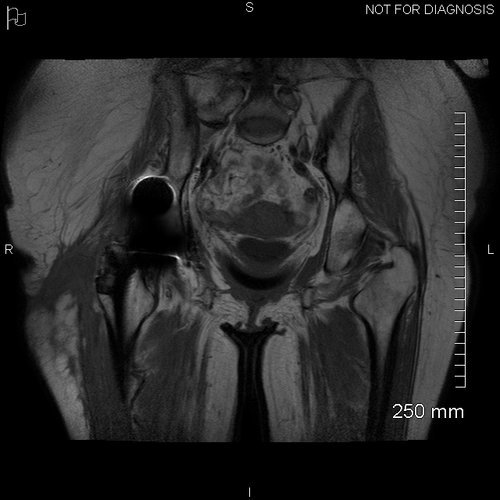

Pre-op MRI demonstrates atrophy of her abductors however there was a tendon attachment present. It demonstrated pockets of fluid around the greater trochanter and in the subcutaneous tissues.